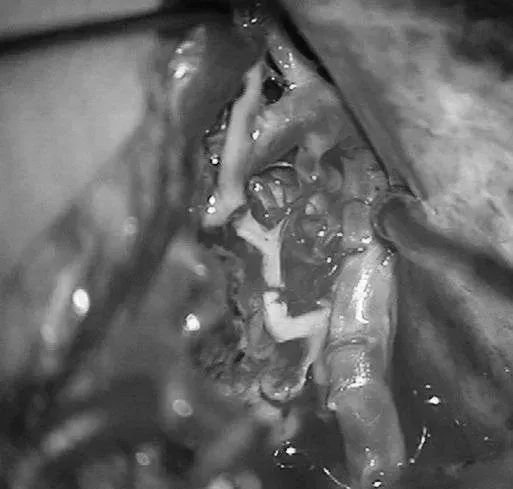

▼显露PCA周围至其ParOccA和CalcA(P2P)分叉

▼沿小脑幕见PCA的大脑脚段(P2A)和硬化的供血支。